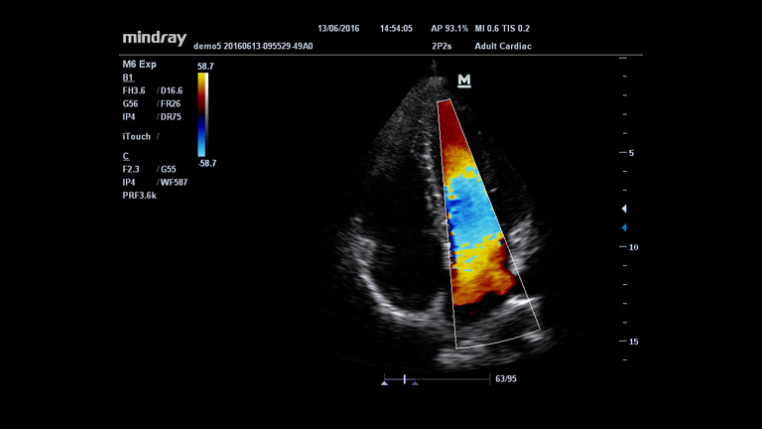

An innovative technology to better visualize tiny vessels and complex flow patterns, based on Mindray's exclusive processing algorithm.

Smart Track

MindrayŌĆÖs unique function: Continuously track the color flow and optimize the best Color box position and angle in real time scanning